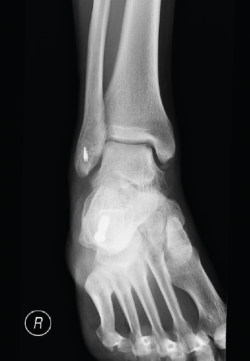

Las clasificaciones de las LOC se basan principalmente en sus características radiográficas. El sistema original de clasificación radiográfica fue desarrollado en 1959 por Berndt y Harty, y basado en proyecciones simples; posteriormente, Loomer añadió el grado V (Tabla 1)(16,17). Antes de esta adición, la clasificación de Berndt y Harty solo abordaba lesiones agudas o fracturas osteocondrales (grados I-IV), mientras que el tipo V (lesión quística) es más característico de las lesiones crónicas (Figura 1).

Figura 1. Radiografía que muestra una lesión osteocondral en la zona medial de la cúpula articular.

Las radiografías convencionales pueden mostrar áreas radiolúcidas o escleróticas en el hueso subcondral; sin embargo, hasta el 50% de las LOC pueden no ser diagnosticadas en radiografías simples(17). Por ello, aunque es útil como herramienta de imagen inicial y debido a esta baja sensibilidad, se recomienda la realización de pruebas adicionales de imagen en presencia de una sólida sospecha clínica.